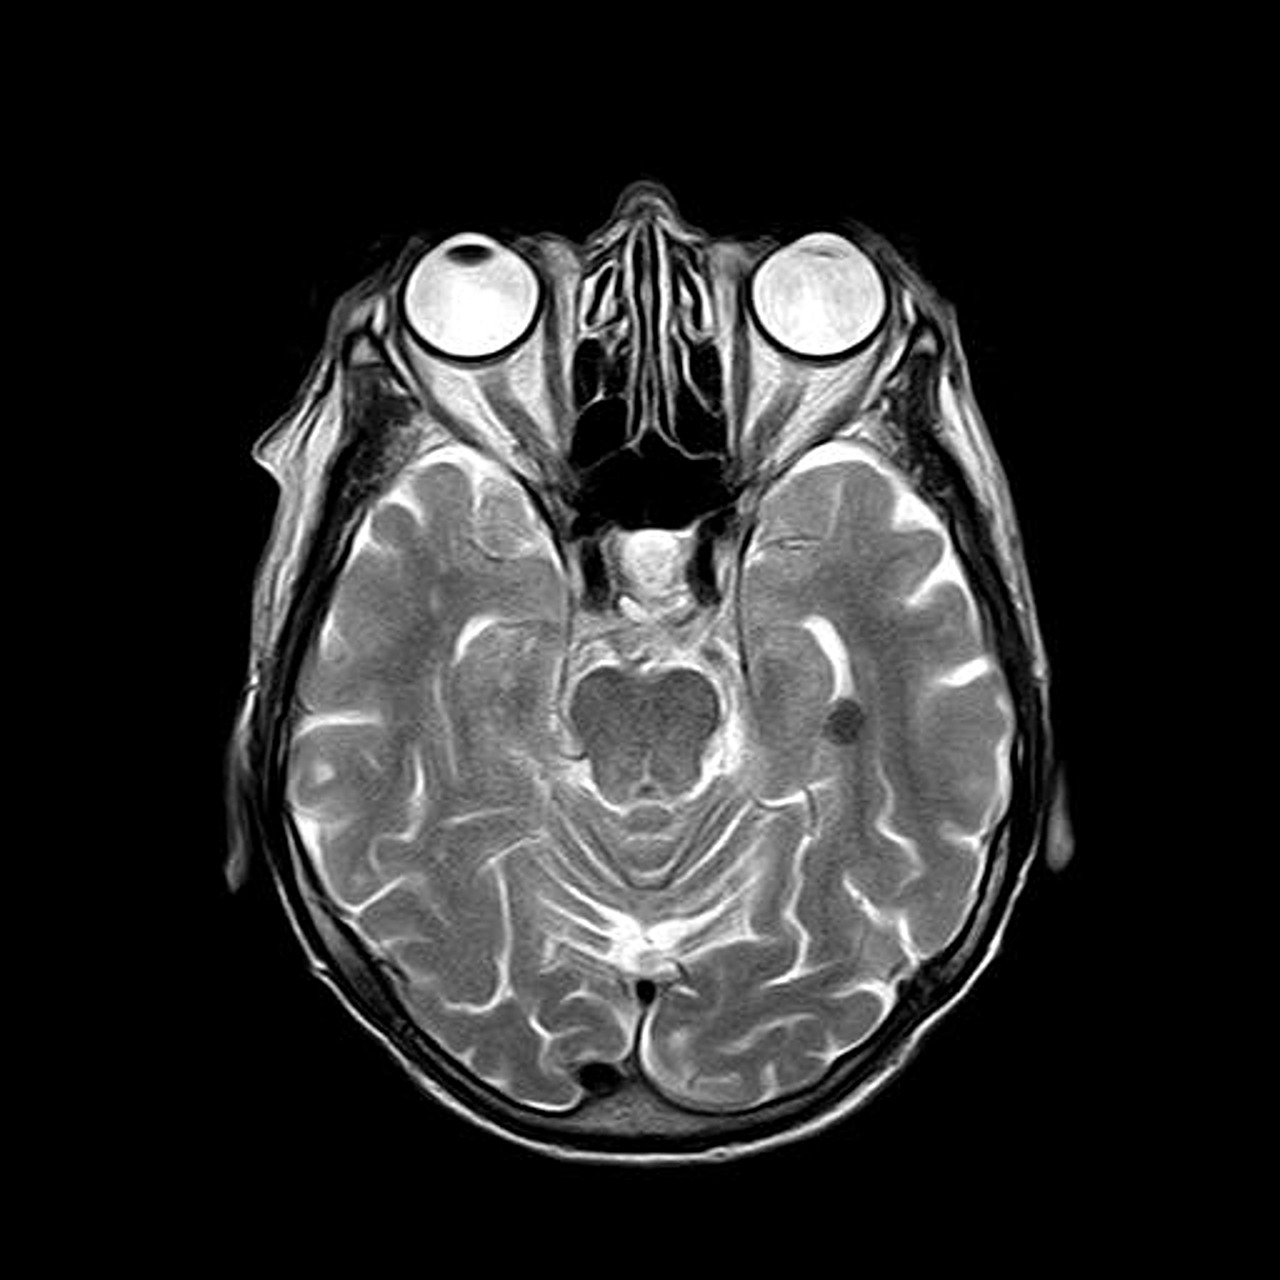

뇌혈관의 정상적인 구조와 기능뇌는 인체에서 매우 중요한 기관으로, 인체 전체 산소 소비량의 약 20%를 차지할 정도로 혈액과 산소에 대한 요구량이 높습니다. 따라서 뇌혈관은 뇌 조직에 필수적인 산소와 영양분을 지속적으로 공급하고 이산화탄소 및 노폐물을 제거하는 중요한 기능을 담당하고 있습니다. 아래에서는 뇌혈관의 정상적인 구조와 기능에 대해 자세히 살펴보겠습니다. 뇌혈관의 구조적 특징 내경동맥(Internal Carotid Artery)뇌 전반부에 혈액을 공급하며, 전대뇌동맥(ACA), 중대뇌동맥(MCA)을 형성합니다.특히, 중대뇌동맥(MCA)은 뇌의 가장 넓은 영역에 혈액을 공급하여 중요합니다.척추동맥(Vertebral Artery)뇌의 후방부에 혈액을 공급하며, 기저동맥을 형성합니다.주로 뇌간, 소뇌..

모야모야병은 만성 진행성 뇌혈관 질환으로, 뇌에 혈액을 공급하는 주요 동맥들이 점진적으로 좁아지거나 폐색되면서 발생합니다. 이 질환의 이름은 일본어 모야모야에서 유래되었는데, 이는 조영술 검사 시 폐색된 혈관 부위에서 미세하게 형성된 대체 혈관들이 흐릿하게 나타나는 모습을 비유한 것입니다. 모야모야병은 주로 소아와 청소년에서 많이 발생하지만, 성인에게도 나타날 수 있으며, 연령대에 따라 임상 증상과 진행 양상이 다르게 나타납니다. 모야모야병의 가장 큰 특징은 뇌의 주요 혈관, 특히 내경부 동맥과 그 가지들이 서서히 협착되거나 폐색되면서 뇌혈류가 감소한다는 점입니다. 이로 인해 뇌조직은 산소와 영양분 공급 부족 상태에 빠지게 되며, 뇌는 이를 보상하기 위해 주변의 소규모 혈관 네트워크를 활성화시켜 우회로를..